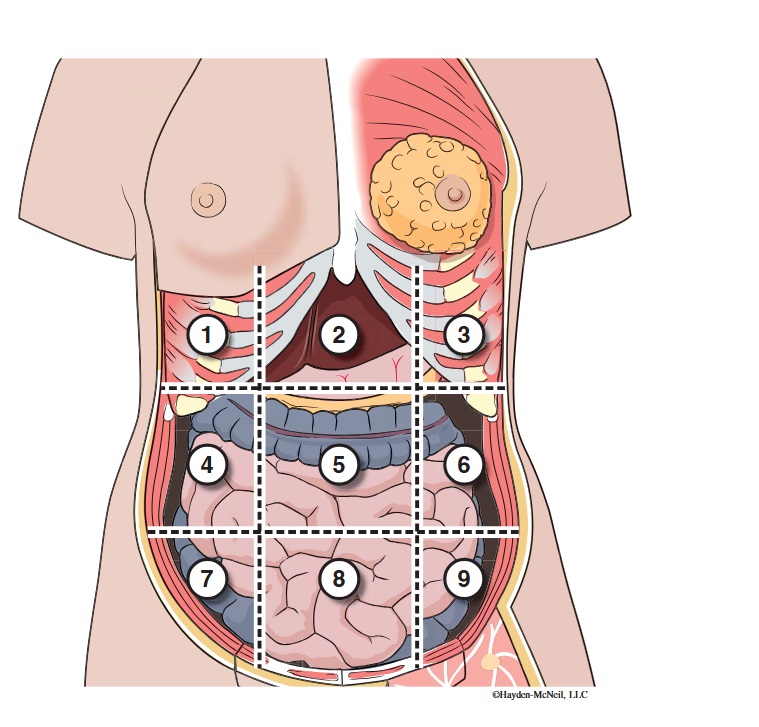

What abdominal region is labeled #1?

right hypochondriac

What abdominal region is labeled #2?

epigastric

What abdominal region is labeled #3?

left hypochondriac

What abdominal region is labeled #4?

right lumbar

What abdominal region is labeled #5?

umbilical

What abdominal region is labeled #6?

left lumbar

What abdominal region is labeled #7?

right iliac/ inguinal

What abdominal region is labeled #8?

hypogastric

What abdominal region is labeled #9?

left illiac/ inguinal

What organs are apart of the right hypochrondriac region?

right lobe of liver, gallbladder, right adrenal gland

What organs are apart of the epigastric region?

pyloric end of stomach, duodenum, pancreas

What organs are apart of the left hypochondriac region?

stomach, spleen, left adrenal gland

What organs are apart of the right lumbar region?

ascending colon, right kidney, portion of small intestine

What organs are apart of the umbilical region?

omentum, mesentery, small intestine

What organs are apart of the left lumbar region?

descending colon, left kidney, portion of the small intestine

What organs are apart of the right iliac/ inguinal region?

cecum of large intestines, appendix, right ovary

What organs are apart of the hypogastric region?

ileum, bladder, uterus

What organs are apart of the left iliac/ inguinal region?

sigmoid colon, left ureter, left ovary